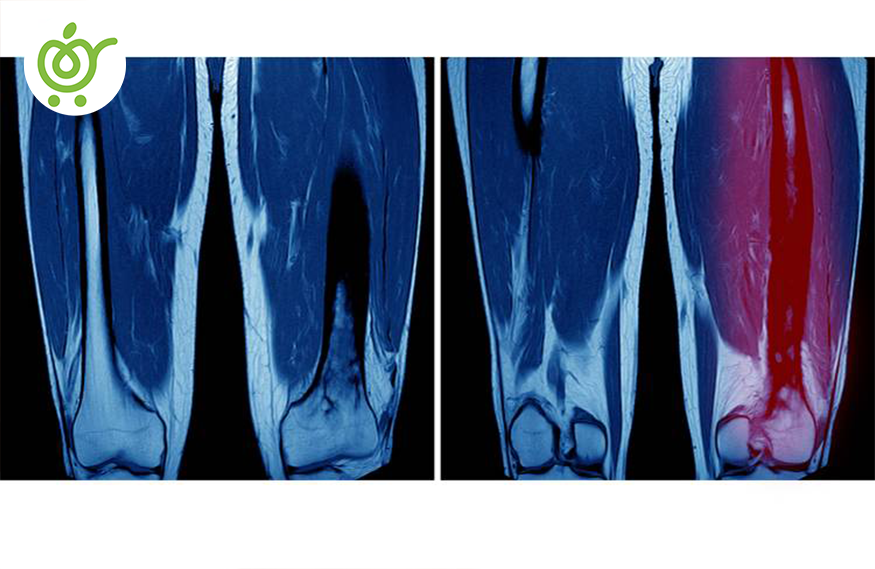

هنگامی که عضلات بیش از حد کشیده میشوند یا اینکه پاره میشوند، شخص دچار کشیدگی ماهیچه شده است. این عارضه معمولاً به دلیل فشار بالایی که به عضله وارد شده است. این مشکل معمولاً در ناحیههای کمر، شانه، گردن و عضلات پشت ران مشاهده میشود. اما نکتهای وجود دارد این است که اگر مشکل بسیار حاد باشد، مراجعه به دکتر ارتوپد ضروری است، در غیر این صورت میتوانید با روشهای خانگی، به درمان آن بپردازید.

اگر ورزش کار هستید و جزء آن دسته از افرادی هستید که دارای تمارین بسیار سنگینی میباشید، اول از همه پیشنهاد میکنیم که اصول تمرینی سالم را رعایت کنید. اگر دچار ضربه دیدگی شدید، حتماً به پزشک ارتوپد مراجعه نمایید؛ زیرا در صورت عدم مراجعه، میتواند آسیبهای دائمی را در بدن شما به جای گذارد.